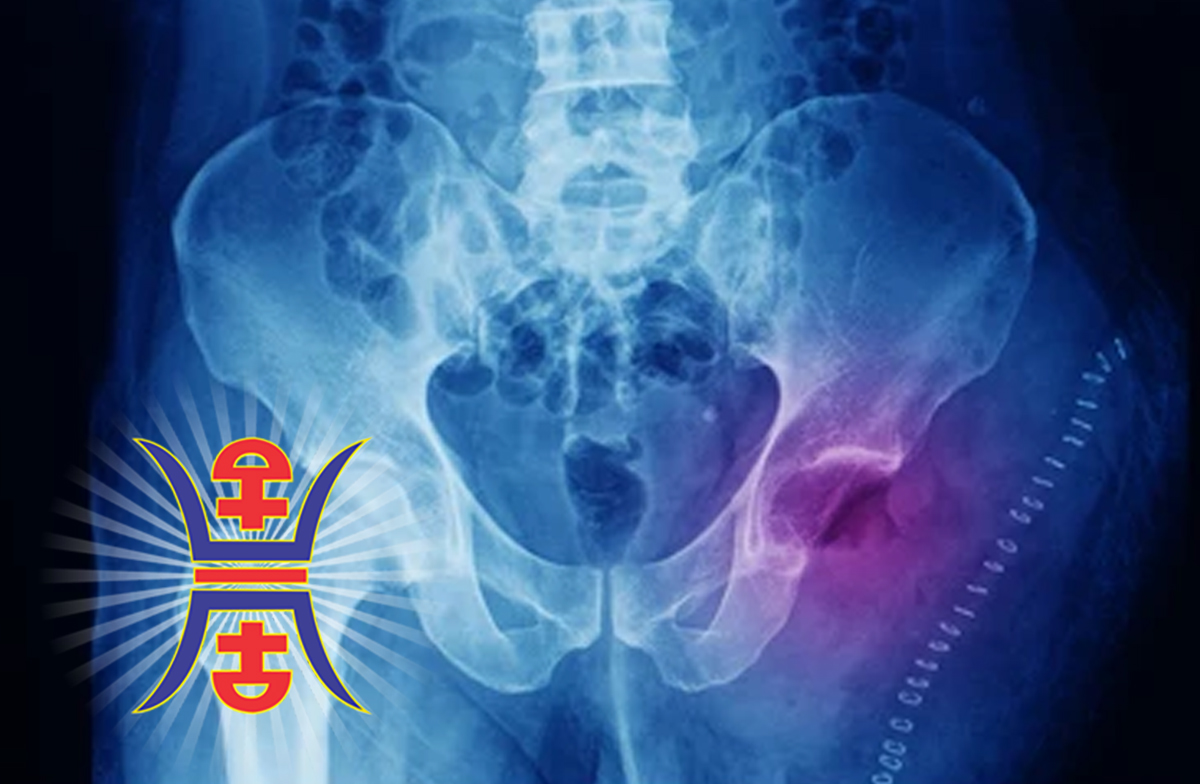

Chondrosarcoma

Chondrosarcoma is a type of cancer that develops in cartilage cells. It is a malignant tumor that can occur in any part of the body where cartilage is present, including the bones and joints. Chondrosarcoma is a rare cancer, accounting for less than 1% of all new cancer cases diagnosed each year.